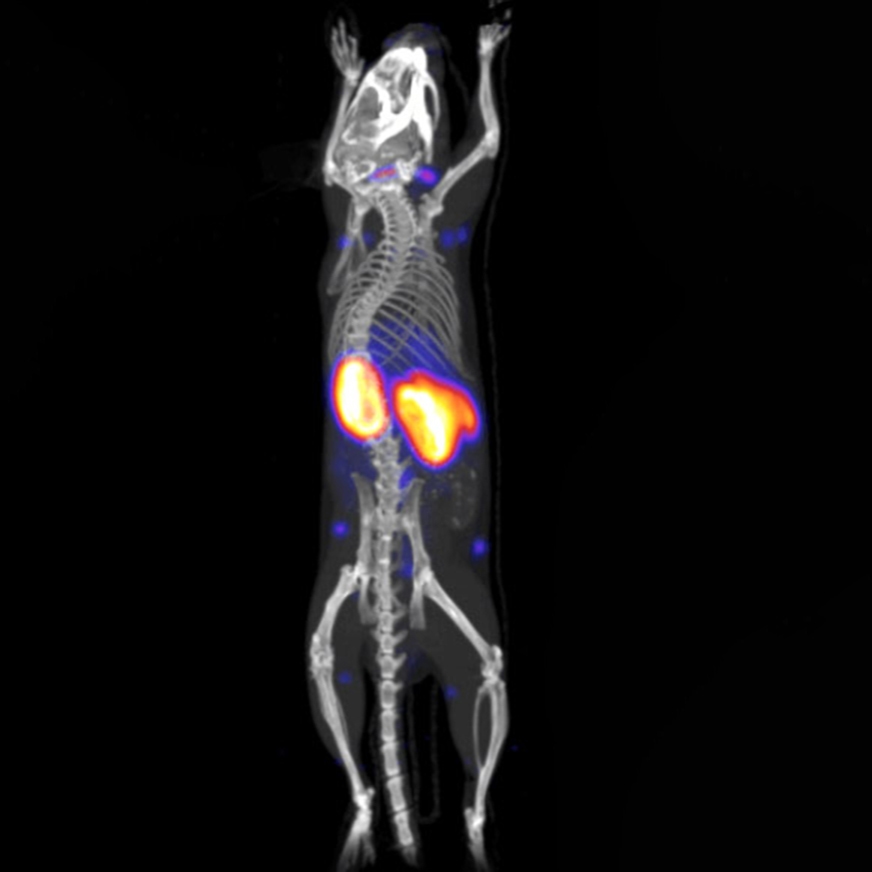

We provide radionuclides that can be used in all modalities of radioactive imaging including PET, SPECT, and Cerenkov Light Imaging (CLI). Molecular imaging with tracers offers excellent sensitivity and accurate quantification of protein targets and low doses. It is possible to investigate the specificity of the antibody for its antigen, binding kinetics, exact localization, internalization, stability of the antibody ligand complex, and biodistribution of the antibody.